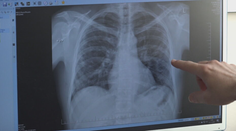

Blížime sa k dôležitej zmene. Rakovinu pľúc zväčša pacientom odhalia až v pokročilom štádiu Chantal R. Staruch 9. 12. 2023

Pľúca Porovnanie snímok pľúc je šokujúce: Po-covidové sú oveľa horšie ako pľúca tuhých fajčiarov Jana Habarová 17. 1. 2021